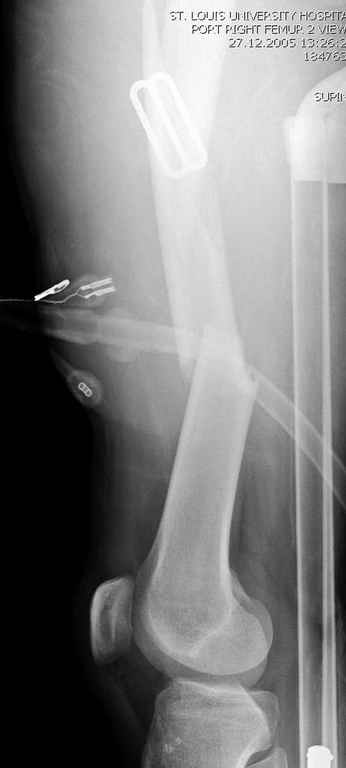

Здесь слайды случая больного с политравмой, включающей сегментарный перелом бедра и повреждение таза с нарушением тазового кольца, разрыв симфиза и перелома крестца зон 2 и 3.

На множественных слайдах важные моменты операции. Хотел бы подчеркнуть, как важно иметь возможности всех необходимых ренгенограмм, включая компютерную томографию и стандартных внутритазовых рентгенограмм (инлет и оутлет).

Djoldas Kuldjanov, MD

Department of Orthopedic Surgery

St. Louis University Medical Center